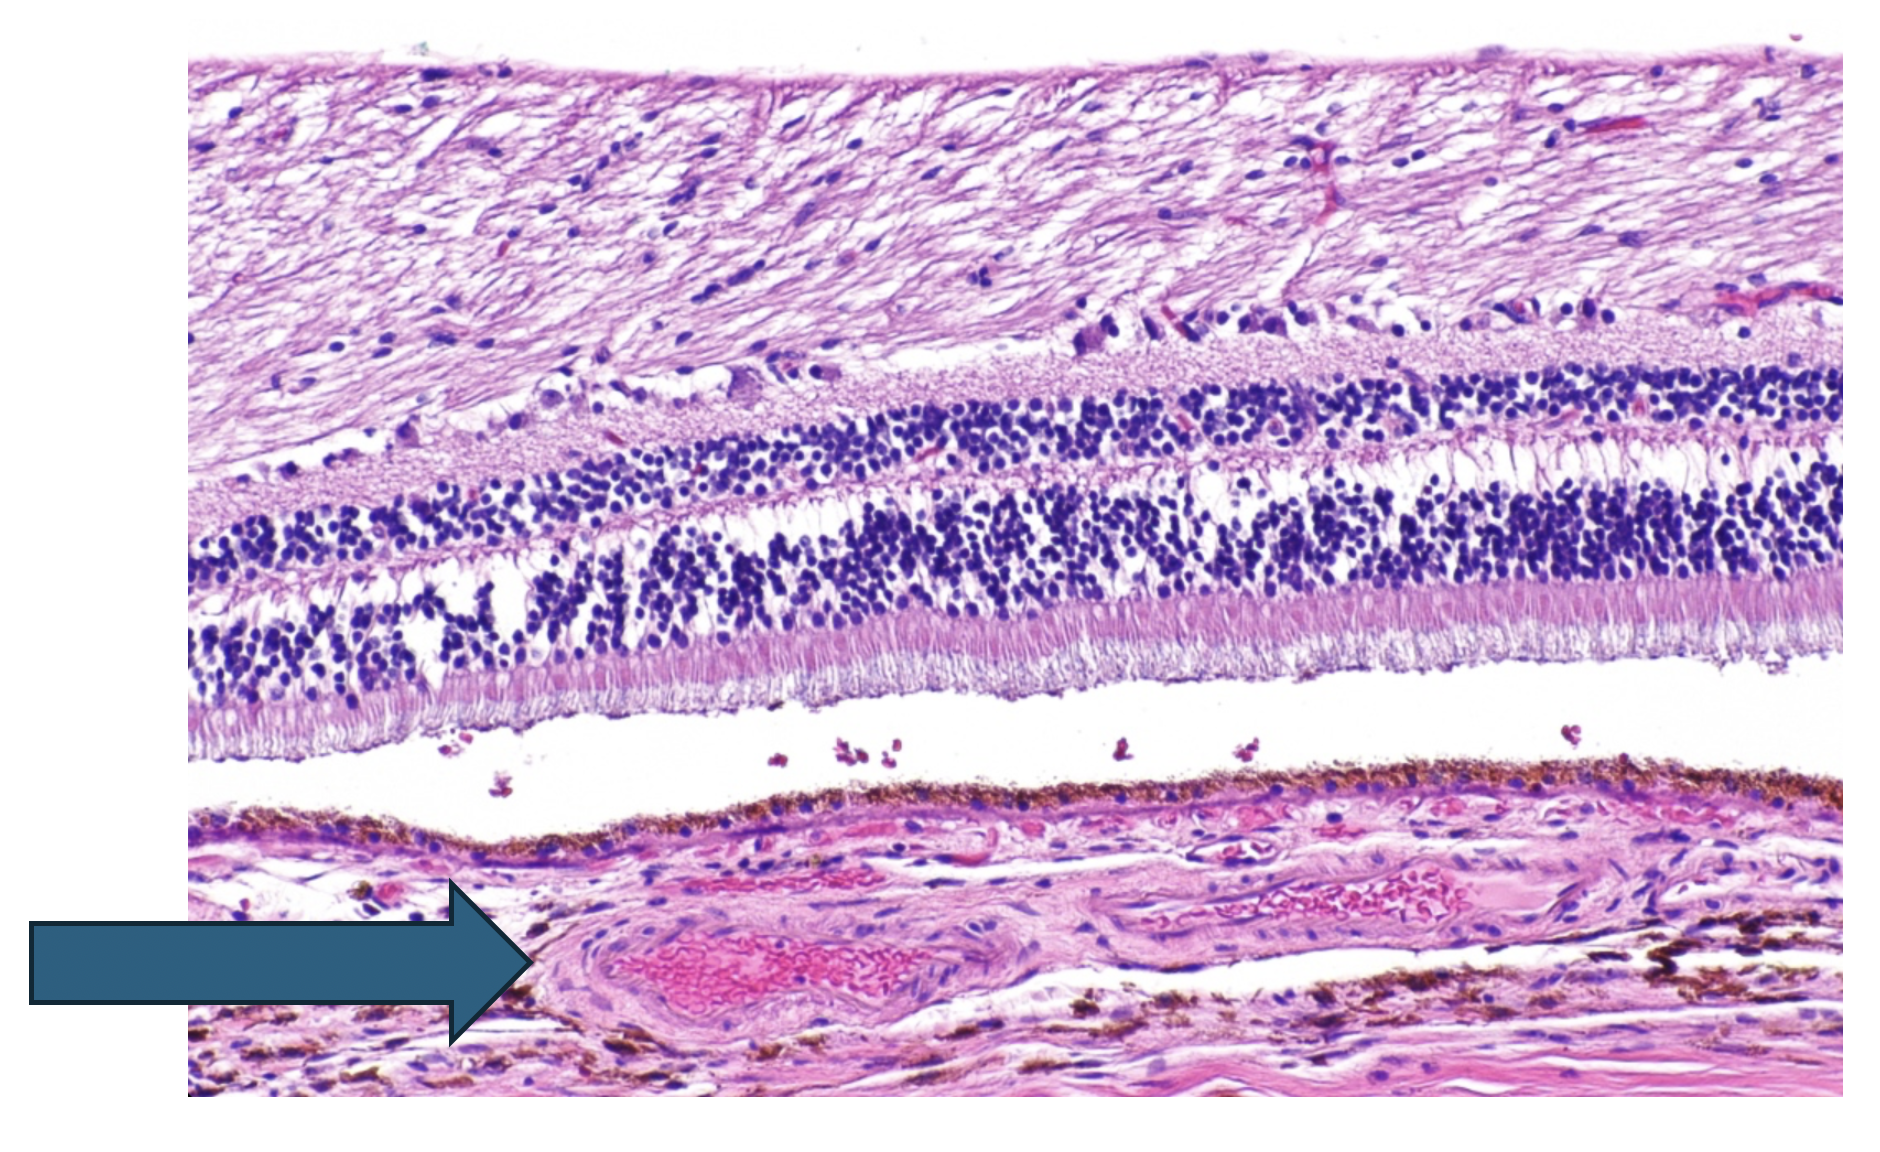

2.92 Im folgenden abgebildet ist ein histologisches Präparat aus dem Auge.

Welche Schicht ist mit dem blauen Pfeil markiert?

Antwortmöglichkeiten

- (A) Nervenfaserschicht Retina

- (B) Innere Körnerschicht Retina

- (C) Pigmentepithel

- (D) Choroidea

- (E) Sklera